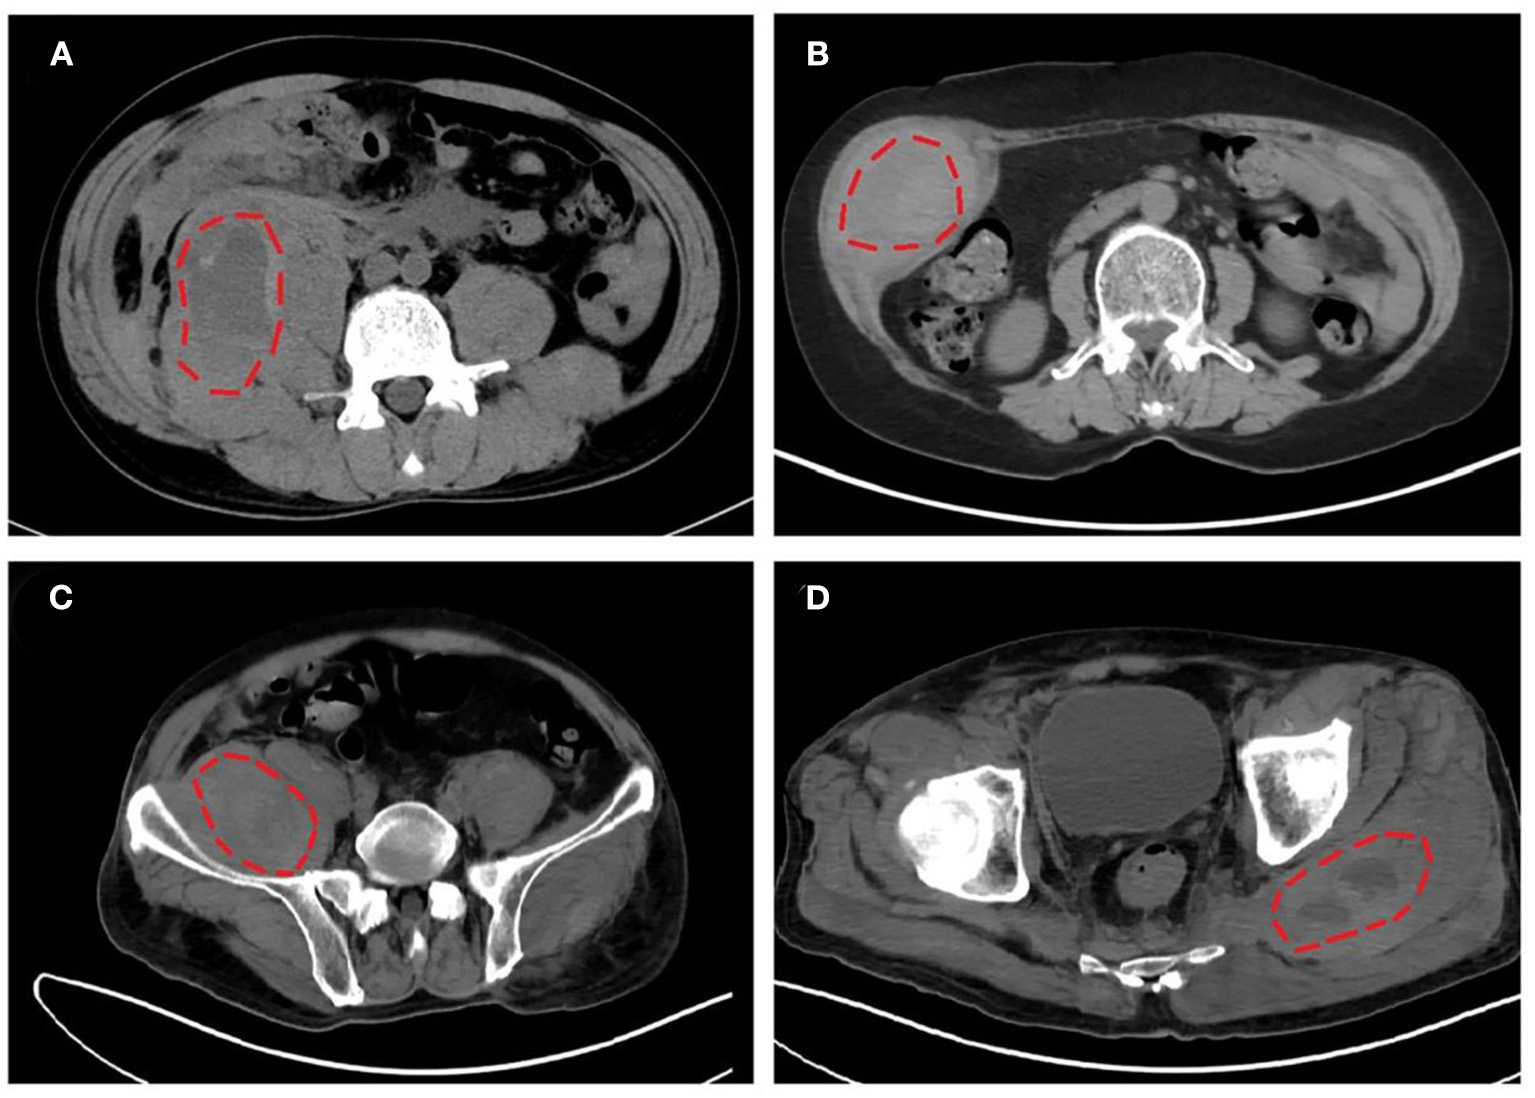

Iliopsoas (including psoas and iliac muscles, 52.2%, 12/23) was the most frequently involved bleeding location, followed by limb girdle muscles (26.1%, 6/23), retroperitoneal muscles (21.7%, 5/23), and rectus sheath muscles (21.7%, 5/23). Representative CT images of intramuscular hematomas of our cases are shown in Figure 2. The locations of hematoma could be briefly categorized into non-palpable deep muscles (e.g., iliopsoas and retroperitoneal muscles) and palpable superficial muscles (e.g., limb girdle muscles and rectus sheath muscles).

Figure 2. Representative computed tomography (CT) images of intramuscular hematomas in our cases. (A) Hematoma in right iliopsoas and psoas of listed case no. 17. (B) Hematoma in right musculi obliquus internus abdominis of listed case no. 18. (C,D) Hematomas in right iliopsoas and left gluteus maximus of listed case no. 20.